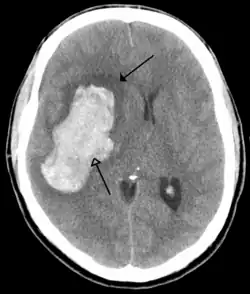

Stroke

A stroke is a decrease in blood supply to an area of the brain causing cell death and brain injury. This can lead to a wide range of symptoms, including the "FAST" symptoms of facial droop, arm weakness, and speech difficulties (including with speaking and finding words or forming sentences).[190] Symptoms relate to the function of the affected area of the brain and can point to the likely site and cause of the stroke. Difficulties with movement, speech, or sight usually relate to the cerebrum, whereas imbalance, double vision, vertigo and symptoms affecting more than one side of the body usually relate to the brainstem or cerebellum.[191]

Most strokes result from loss of blood supply, typically because of an embolus, rupture of a fatty plaque causing thrombus, or narrowing of small arteries. Strokes can also result from bleeding within the brain.[192] Transient ischaemic attacks (TIAs) are strokes in which symptoms resolve within 24 hours.[192] Investigation into the stroke will involve a medical examination (including a neurological examination) and the taking of a medical history, focusing on the duration of the symptoms and risk factors (including high blood pressure, atrial fibrillation, and smoking).[193] Further investigation is needed in younger patients.[194] An ECG and biotelemetry may be conducted to identify atrial fibrillation; an ultrasound can investigate narrowing of the carotid arteries; an echocardiogram can be used to look for clots within the heart, diseases of the heart valves or the presence of a patent foramen ovale.[194] Blood tests are routinely done as part of the workup including diabetes tests and a lipid profile.[194]

Some treatments for stroke are time-critical. These include clot dissolution or surgical removal of a clot for ischaemic strokes, and decompression for haemorrhagic strokes.[195][196] As stroke is time critical,[197] hospitals and even pre-hospital care of stroke involves expedited investigations – usually a CT scan to investigate for a haemorrhagic stroke and a CT or MR angiogram to evaluate arteries that supply the brain.[194] MRI scans, not as widely available, may be able to demonstrate the affected area of the brain more accurately, particularly with ischaemic stroke.[194]